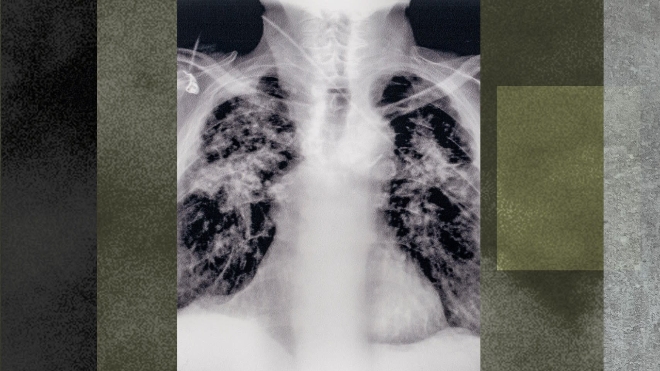

이미지 확대보기규소폐증은 실리카 먼지를 오랫동안 흡입하면서 발생하는 직업병으로 한번 발병하면 폐 기능이 점점 악화돼 평범한 일상조차 힘들어진다.